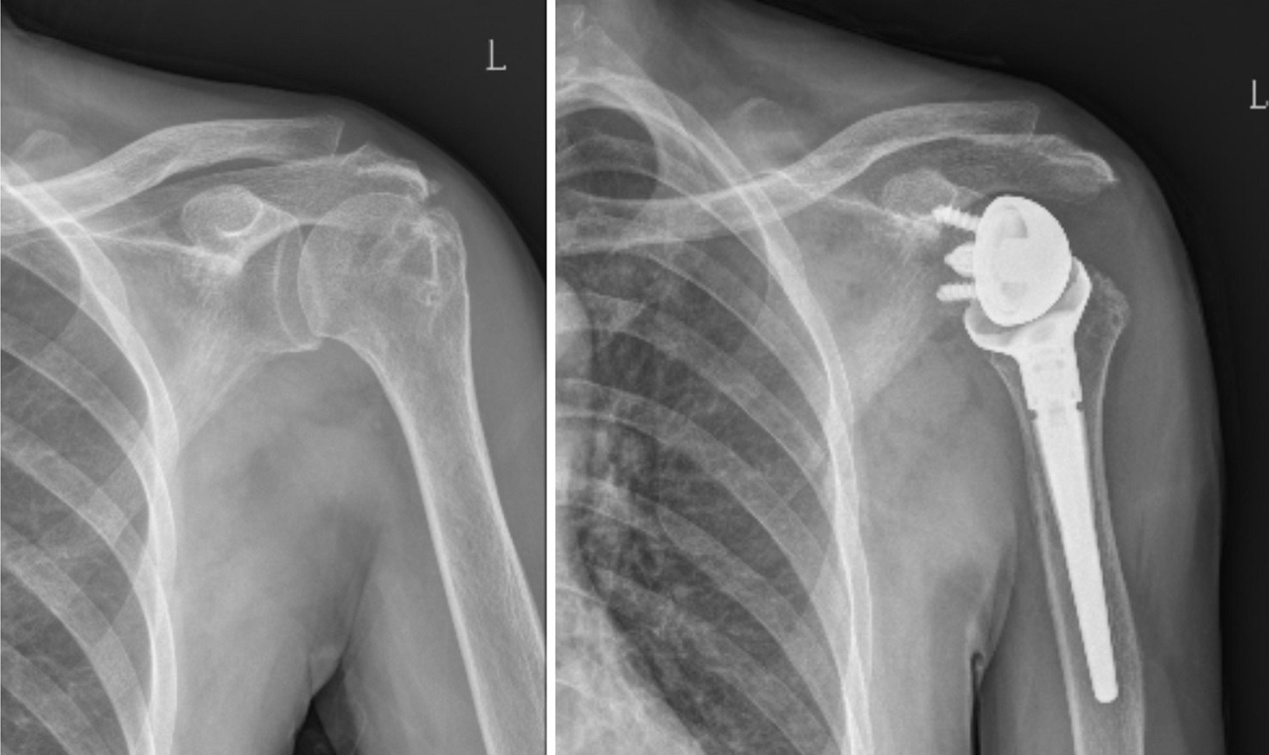

该患者为老年女性,因肩袖撕裂而导致肩部疼痛逐渐加重。近日,她慕名来烟台山医院运动医学科,运动医学科成功主任经过细致查体并结合病史和影像学检查,诊断患者所患为巨大不可修复肩袖撕裂。针对此类肩关节疾病,传统的肩关节置换术并不能改善因肩袖巨大撕裂导致的肩关节功能障碍。经与患者沟通,考虑到患者要求缓解疼痛和改善功能的需求,最终决定实施反式肩关节置换术为其治疗。

据悉,针对巨大肩袖撕裂,以往可选用的方法包括肩峰下球囊植入术、肩袖部分修复术、上关节囊重建术以及背阔肌转位术等,它们的优缺点各不相同,但远期效果皆不确切。反式肩关节置换术被认为是过去40多年,肩关节重建手术中最具影响力的技术革新之一。目前已广泛应用于治疗肩关节巨大肩袖撕裂,尤其是已经成为解决不可修复性巨大肩袖撕裂的终极方案。但由于该手术技术难度高,学习曲线长,目前省内能够开展此项手术的医院为数不多。

成功主任表示,“反式人工全肩关节置换术(RTSA)是一种创新的手术技术,其通过翻转传统肩关节的解剖结构关系,解决了长期困扰患者的肩关节稳定性和功能问题。这一手术利用三角肌功能来替代肩袖的功能,设计上通过旋转中心内移及下移肱骨假体增大三角肌张力,在几乎不借助肩袖肌肉的情况下,更好地发挥三角肌功能,恢复肩关节正常活动范围和力量,能极大改善患者肩关节疼痛及功能障碍。”